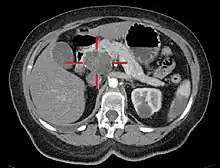

Axial CT image with IV contrast and added color. Cross lines towards top left surround a macrocystic adenocarcinoma of the pancreatic head.

Abdominal ultrasonography of pancreatic cancer (presumably adenocarcinoma), with a dilated pancreatic duct to the right.

Medical imaging techniques, such as computed tomography (CT scan) and endoscopic ultrasound (EUS) are used both to confirm the diagnosis and to help decide whether the tumor can be surgically removed (its "resectability").[12] On contrast CT scan, pancreatic cancer typically shows a gradually increasing radiocontrast uptake, rather than a fast washout as seen in a normal pancreas or a delayed washout as seen in chronic pancreatitis.[50] Magnetic resonance imaging and positron emission tomography may also be used,[11] and magnetic resonance cholangiopancreatography may be useful in some cases.[30] Abdominal ultrasound is less sensitive and will miss small tumors, but can identify cancers that have spread to the liver and build-up of fluid in the peritoneal cavity (ascites).[12] It may be used for a quick and cheap first examination before other techniques.[51]